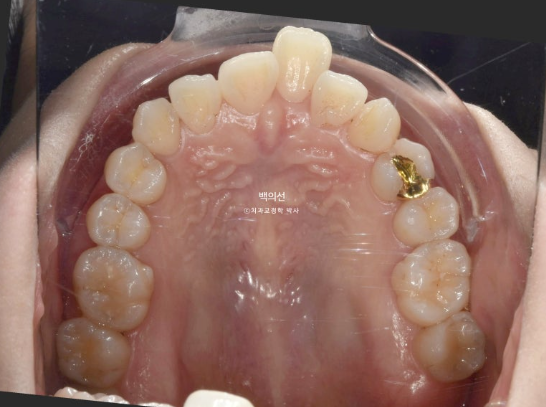

앞니 덧니가 보입니다.

중심선이 약 2mm 어긋나 있습니다.

앞니 뻗침은 심한 편 입니다.

인비절라인을 원하셔서 인비절라인 발치교정을 권유드렸습니다.

작은어금니 4개를 발치하기로 했습니다.

첫번째 세트의 장치는 총 80개가 나왔습니다.